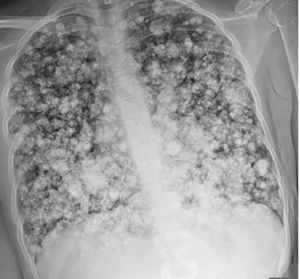

A 21-year-old woman presented to the emergency department with an 8-month history of swelling and pain in the right thigh. MRI of the right leg revealed a large periosteal femoral mass and thrombus in the right femoral vein, for which she received anticoagulation therapy. The patient subsequently experienced dyspnea and pleuritic chest pain, and a chest x-ray was done. What is the likely A-Pulmonary embolism B-Pulmonary sarcoidosis C-Eosinophilic granulomatosis with polyangiitis D-Chondroblastic osteosarcoma E-Miliary tuberculosisdiagnosis?